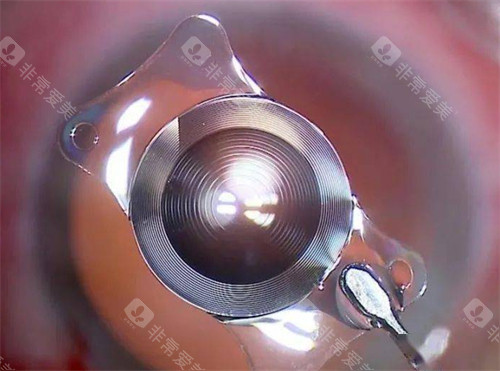

白内障正规开展了多种白内障手术,包括超声乳化白内障吸除术等,手术技术成熟,术后结果良好。

此外,科室还开展了一些潮流的眼科手术技术,如飞秒激光辅助白内障手术等,大大提高了手术的可靠性和有效性。